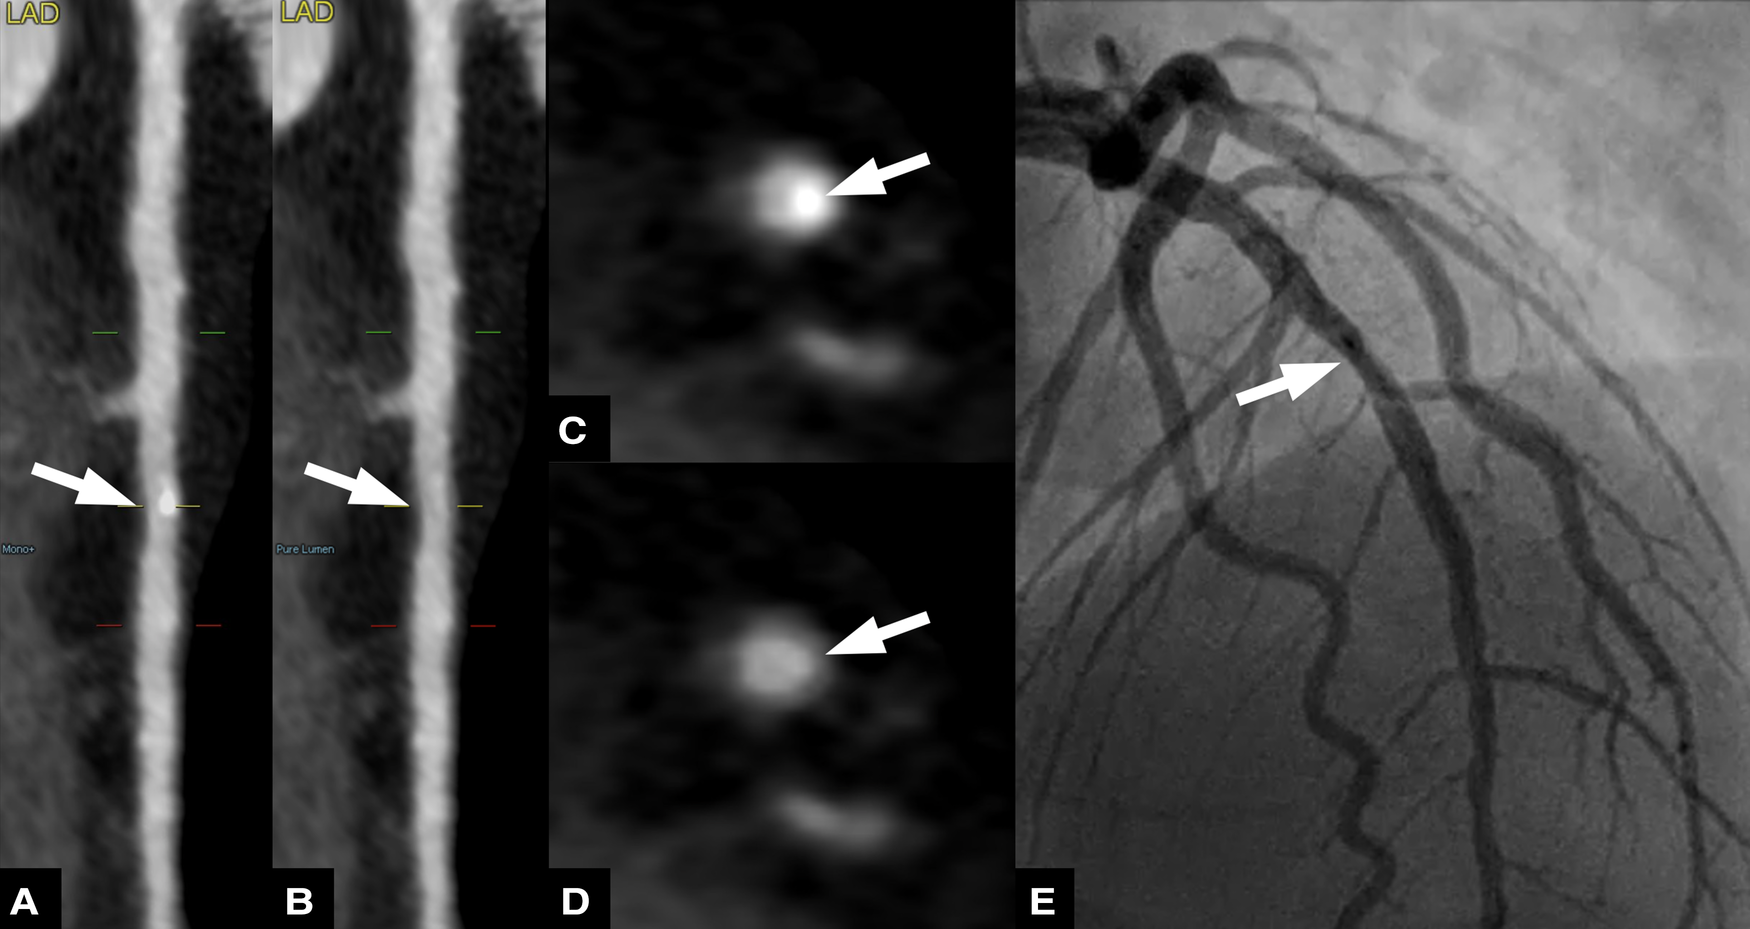

Figure 5

Fifty nine-year-old male patient with suspected coronary artery disease. Straightened multiplanar reformations of conventional (A) and virtual non-calcium (VNCa) images (B) show calcified and subtracted calcified plaques, respectively, in the mid left anterior descending artery (LAD). Corresponding axial images show the calcified plaque (C) and the vessel lumen after subtraction (arrow) (D) invasive coronary angiography (E) confirmed the presence of a mild stenosis in the proximal LAD.